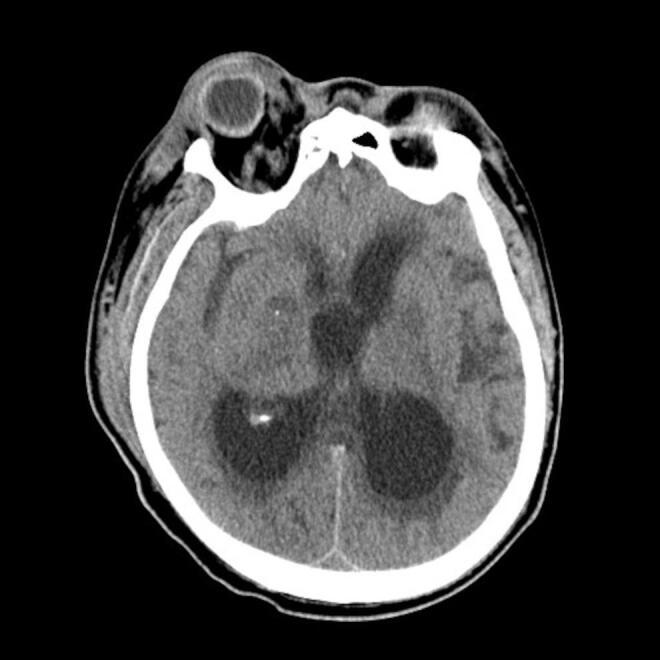

Meningitis-related acute hydrocephalus is rare, challenging to diagnose, and has a high mortality rate.

Here we describe the case of a 76-year-old patient diagnosed with bacterial meningitis who developed acute hydrocephalus and subsequently died.

Although meningitis-related acute hydrocephalus is usually non-occlusive, occlusive hydrocephalus may also occur. Moreover, worsening hydrocephalus despite cerebrospinal fluid drainage should prompt a diagnosis of obstructive hydrocephalus. In such conditions, potential management strategies include ventriculoperitoneal shunt and endoscopic third ventriculostomy.

In patients with meningitis-related hydrocephalus, worsening despite appropriate antibiotic administration, treatment may be complicated by ventriculitis and obstructive hydrocephalus, which can be fatal. If intracranial pressure is not medically controlled, bilateral decompression craniectomy should be considered as a potential management strategy.